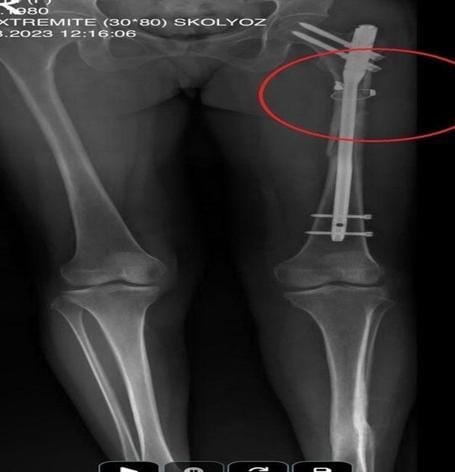

Cinayetin ardından aynı silahı sevgilisine çeviren Sarıkaya, Fatma O.'yu 8 kurşunla yaraladı. Olayın ardından arkadaşı Özaslan'ın cesedini önce çarşafa, ardından kokuyu engellemek amacıyla streç filme sarıp bantlayan zanlı, evde dehşet verici bir düzen kurdu. Yaralı haldeki sevgilisinin hastaneye gitmesine izin vermeyen Sarıkaya, eczaneden aldığı sargı bezi ve ilaçlarla kadına pansuman yaptı. İddianameye göre Sarıkaya, yaralı halde evde rehin tuttuğu Fatma O.'ya 21 gün boyunca cinsel saldırıda bulundu.